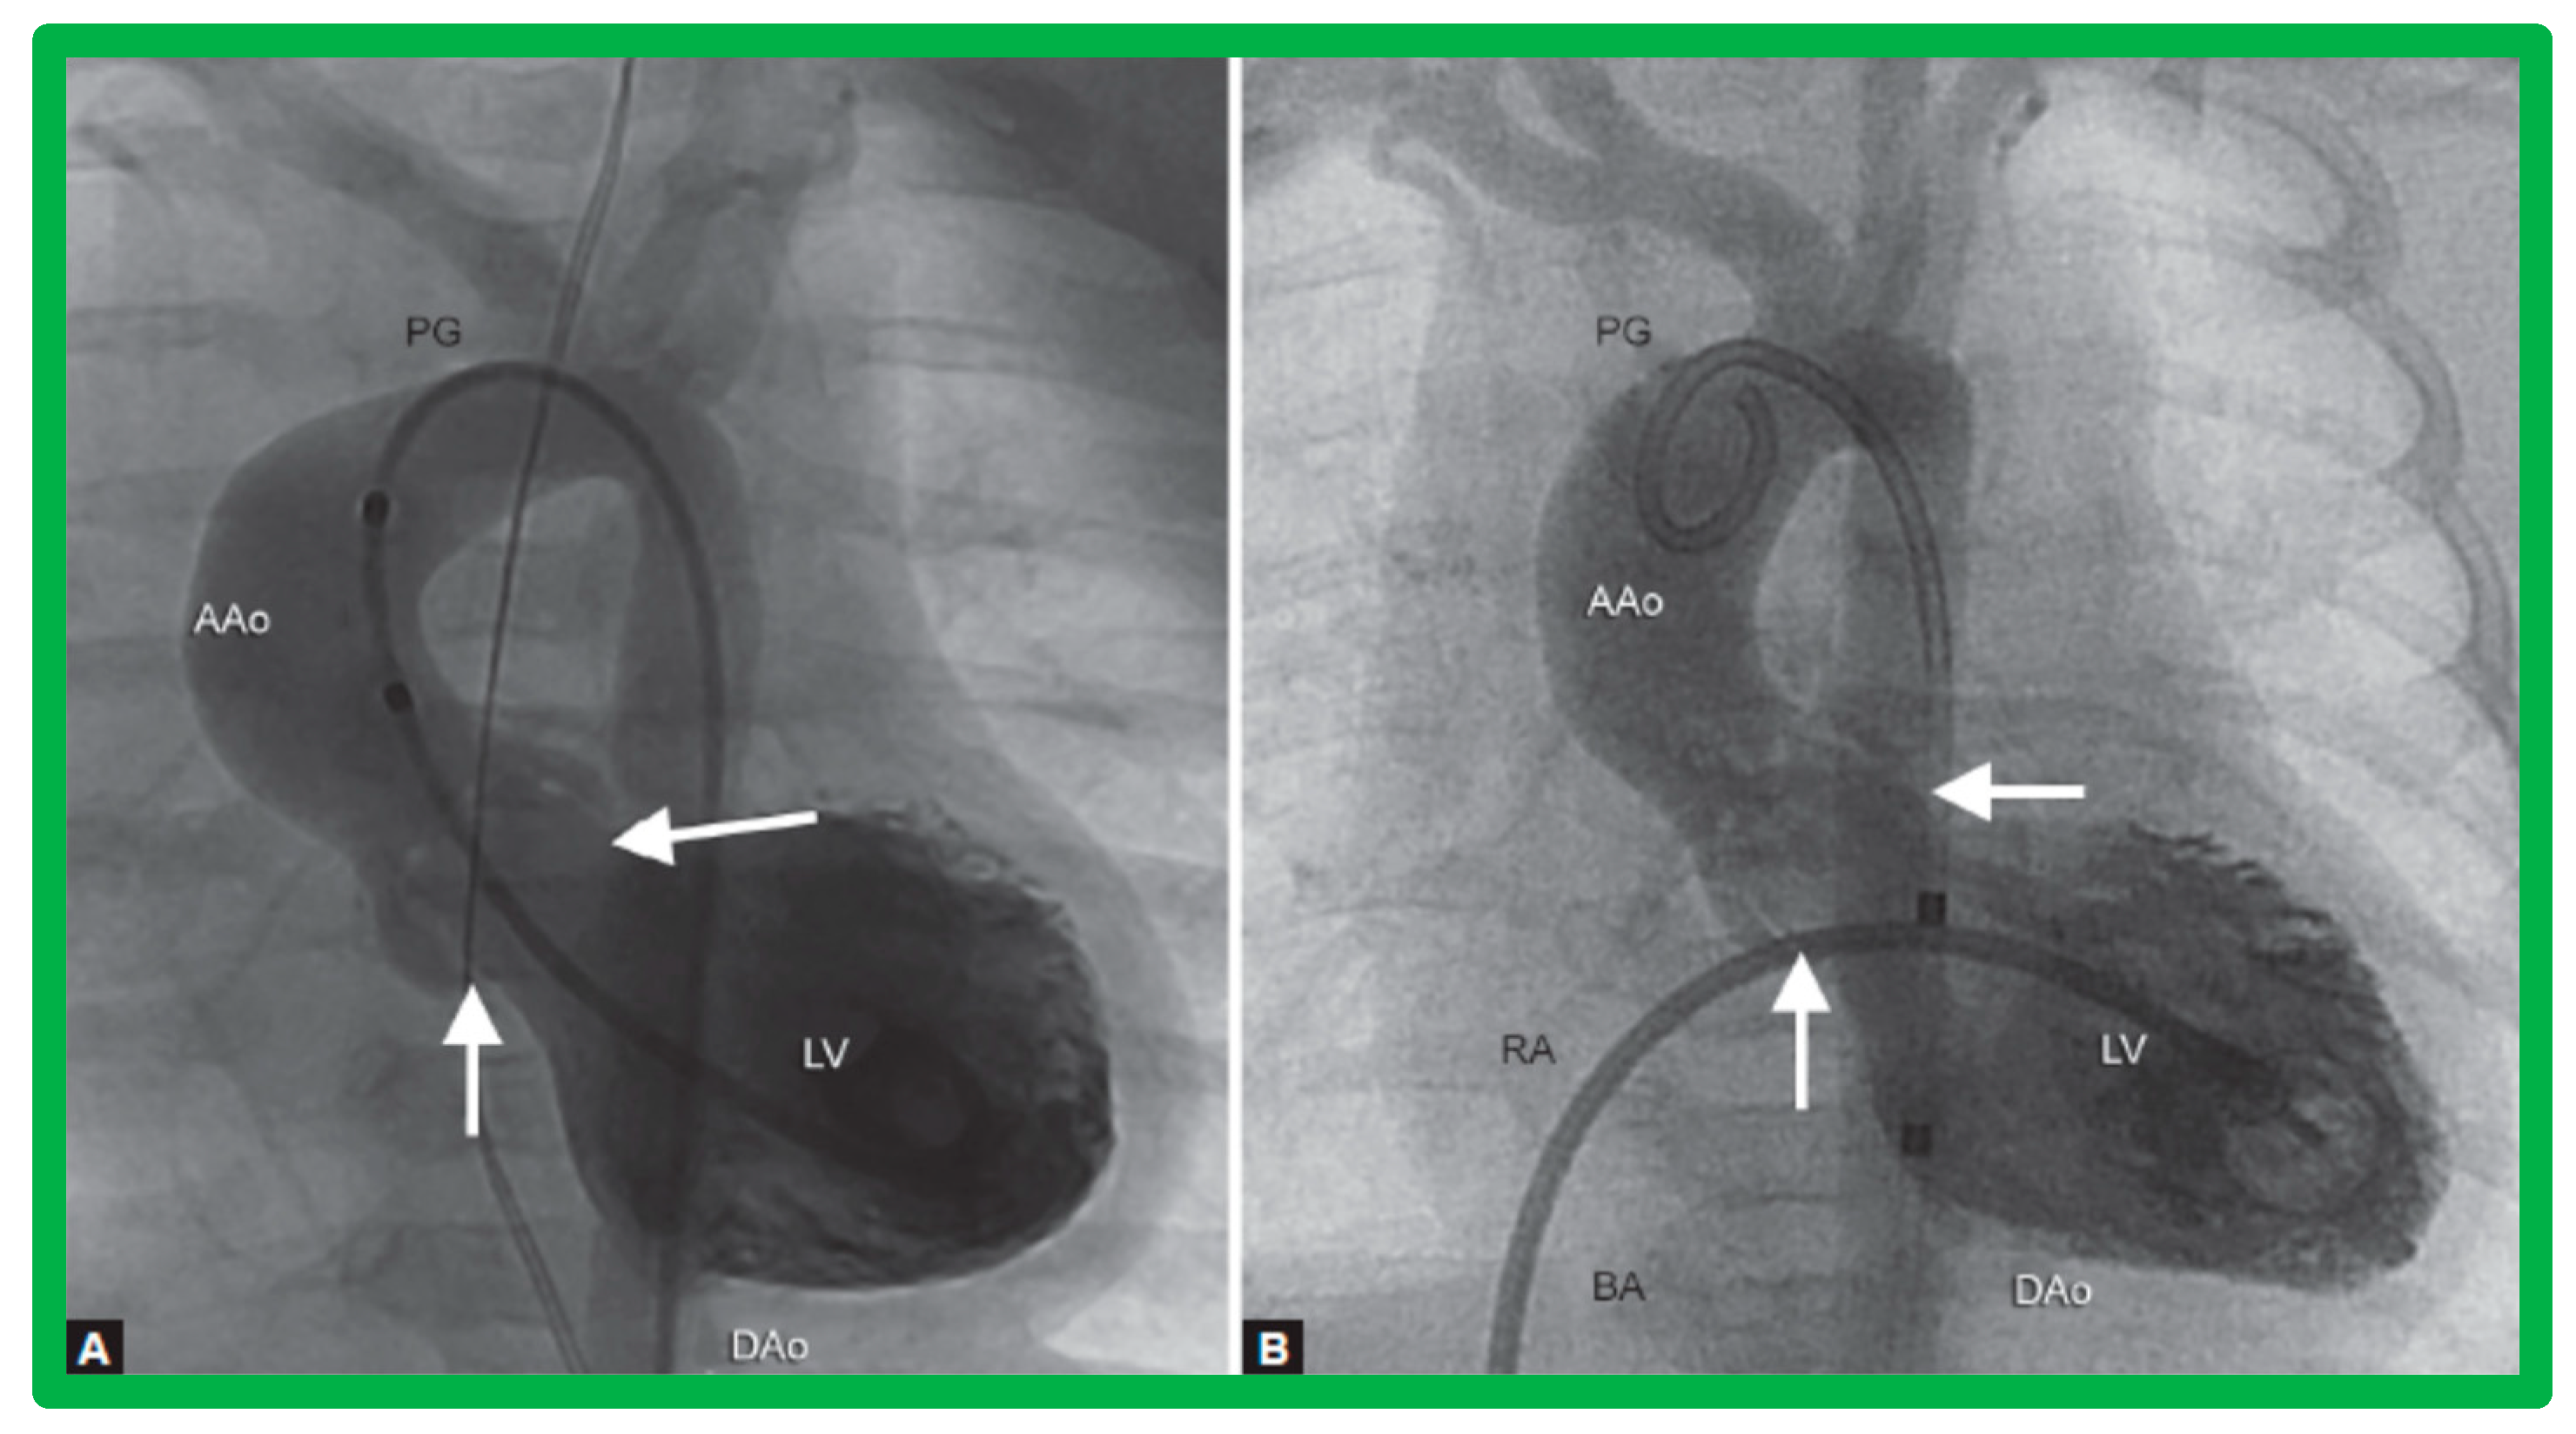

3.2. Aortic Stenosis

Aortic Stenosis in the Fetus